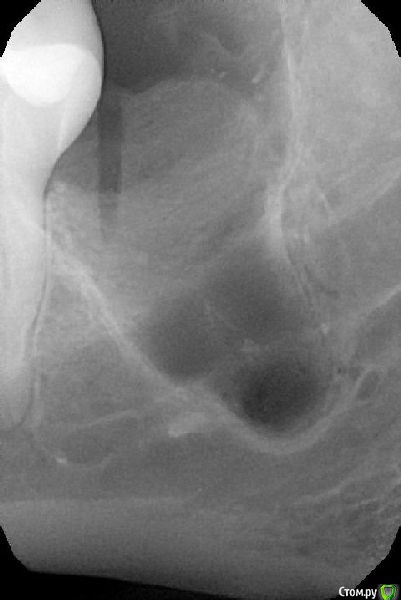

Alena.vsk Опубликовано 30 июля, 2016 Поделиться Опубликовано 30 июля, 2016 (изменено) Здравствуйте, уважаемые специалисты и посетители форума! 4 недели назад был удален 38й зубик. Хирург изначально до операции сделал панораму и 3д томограмму, чтобы понять как проходит нерв, и сообщил, что в моем случае крайне вероятно (99%) возникновение парастезии, до полугода. Т.к. нерв раздавлен зубом, и удалить зуб, не задев нерв, практически невозможно.Удалили относительно быстро: на всё не больше часа, включая уколы и разговоры.Доктор напоследок осмотрел лунку, хотел понять видно ли визуально нерв.В итоге сказал что нерв не виден, остался доволен и уже оценив результат, сообщил что вполне возможно парастезия меня обойдет стороной.Но увы, не обошла: подбородок и нижняя губа онемевшие. Язык и десна - в норме. Заживление в целом проходило и проходит нормально, не считая долго сходившего отека (около 10 дней), но это скорее моя склонность к отекам. Первые дней 10:-очень ломило 31-33 зубы + сильная чувствительность. ПРиходилось пить обезбаливающее.-Подбородок не чувствовал практически ничего. Только при сильном прикосновении чувствовались какие-то оооочень далекие ощущения, даже не похожие на прикосновения. Можно сказать, около 3% чувствительности, и то какой-то не правильной.- нижняя губа первые 10 дней была чуууточку более чувствительна, чем подбородок. Но вместо прикосновений - ощущала только жжение. И даже если губу не трогать - жгло почти постоянно. На сегодня (4 недели после удаления):-Боль 31-33их зубов полностью прошла.-Жжение нижней губы стало намного слабее, но пока слегка сохраняется, и только при мимике и прикосновении. -Подбородок по прежднему "мертвый", подвижек никаких по сравнению с первыми днями. Чувствует только температуру: холодное чувствует хорошо, горячее плохо, только если сочень горячее прикладывать. Изредка чешется, чем доставляет мучения, т.к. "прочесать" зудящее место невозможно. Но кажется (надеюсь не кажется), в кайме губы появилось легкое ощущение чувствительности, похожее на правильное нормальное ощущение. Но только в кайме. В толще губы по прежднему только жжение при прикосновении. с 20ого дня после удаления начала принимать: 1 таб Мильгаммы утром, 1 таб Нейромультивит вечером (по рекомендации хирурга) Собственно ВОПРОС Подбородок и губа- это одна и та же ветка нерва? Можно ли считать, что раз в кайме губы появилась какая-то слабая чувствительность - то значит нерв не перебит совсем и подбородок с толщей губы тоже теперь гарантированно восстановятся?Или же это разные ветки нерва, и если кайма восстановилась, то не факт что восстановится и все остальное? На всякий случай прикладываю рентген и томограмму до, и рентген после. Хирург у меня хороший, пошла к нему по рекомендации от 4х друзей, но очень уж неразговорчивый. На все мои вопросы отвечал "время покажет", давал назначения, промывал лунку и быстренько выпроваживал.Сейчас он на несколько недель в отъезде. И еще один ВОПРОС! По рентгену "после" можно понять, нормально ли затягивается лунка костной тканью? Визуально оценить не могу, т.к. десну зашивали частично, оставлен только разрез между щекой и зубами (разрез по прежднему есть, пока не заживает). Рентген сделан сегодня, т.е. лунке уже месяц. ДО ПОСЛЕ Изменено 30 июля, 2016 пользователем Alena.vsk Ссылка на комментарий